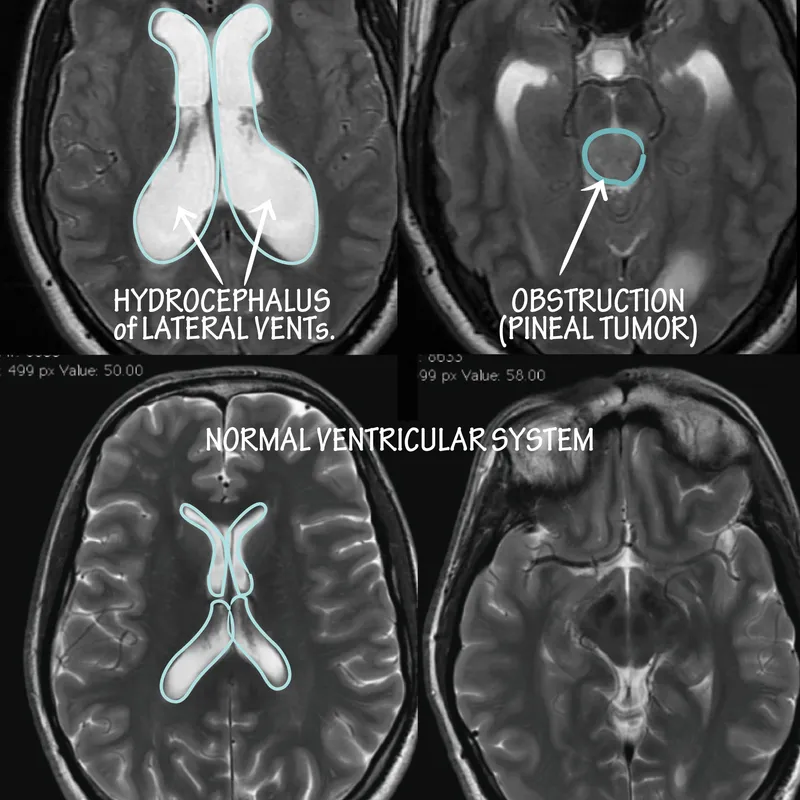

- Hydrocephalus: Excess CSF.

- Communicating: ↓Absorption (post-meningitis, SAH). Symmetric ventricular enlargement.

- Non-communicating (Obstructive): Flow block (aqueductal stenosis, tumor). Proximal ventricular dilation.

- Aqueduct of Sylvius: narrowest point; its obstruction causes non-communicating hydrocephalus.

- Communicating hydrocephalus results from impaired CSF absorption by arachnoid villi.